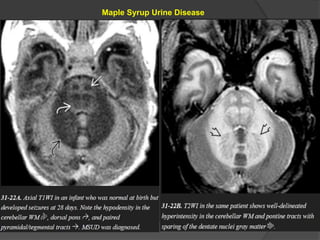

Maple Syrup Urine Disease

Symptoms usually develop within a few days after birth and

include poor feeding, lethargy, vomiting, and seizures.

In severe cases, the urine smells like maple syrup or burnt

sugar.

NECT scans

show profound hypodensity in the myelinated WM with

vasogenic edema in the (Areas of early myelination) dorsal

brainstem, cerebellum, cerebral peduncles, and posterior limb

of the internal capsule.

MR scans show striking T2/FLAIR hyperintensity with relatively

crisp margins.

DWI shows restricted diffusivity